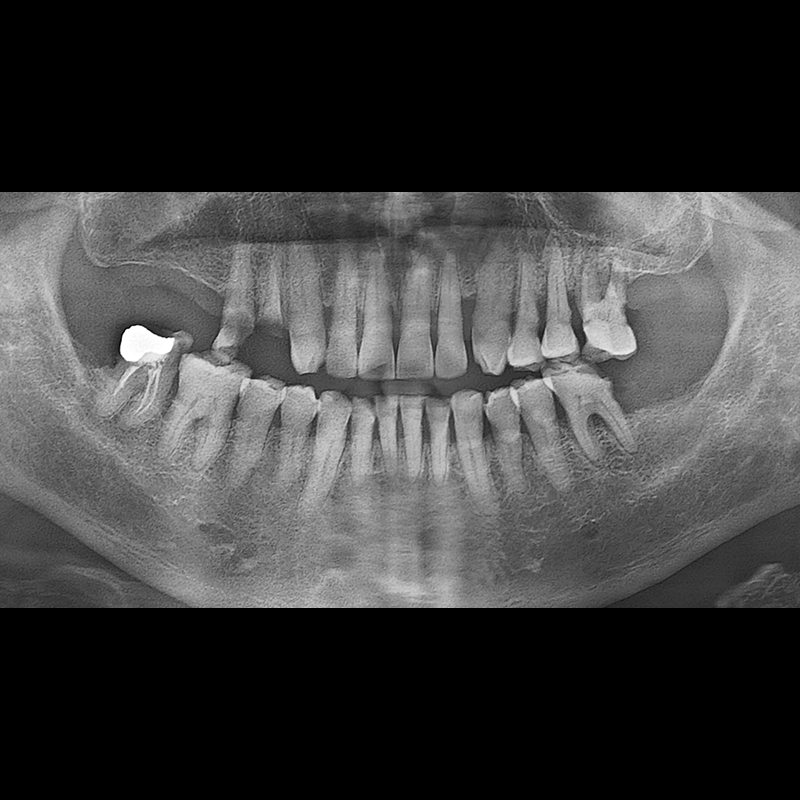

BEFORE AFTER

임플란트 전후사진 2025.05.30

결손된 치아 부분과 살리기 힘든 치아 위치에 임플란트를 식립하였습니다.